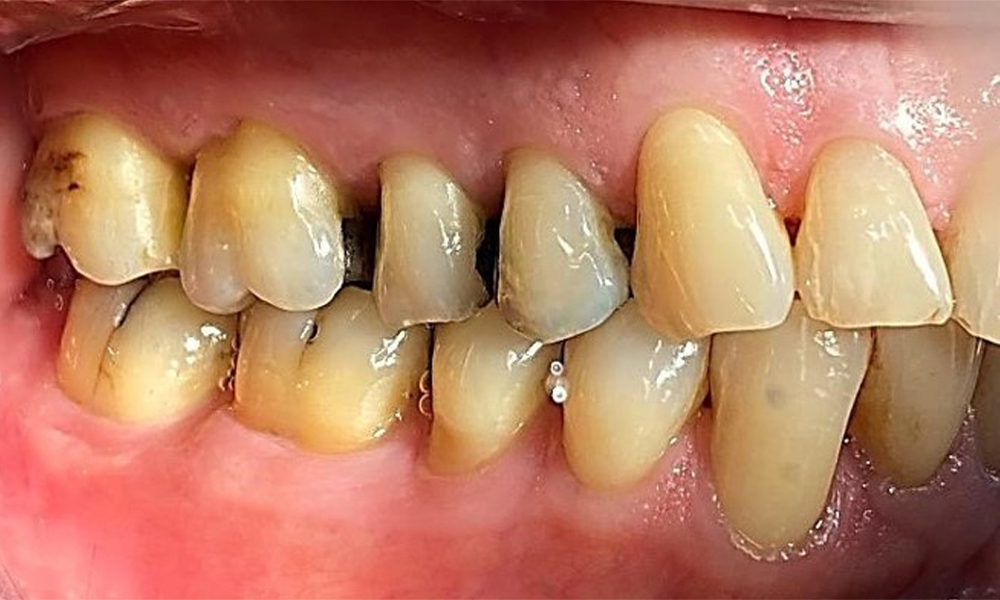

Lateralansicht rechts. Verlust der interdentalen Papillen. © Dr. R. Krapf

Abb. 3 Lateralansicht rechts. Verlust der interdentalen Papillen. © Dr. R. Krapf

Der Patient hat ein vollbezahntes Gebiss mit 28 Zähnen, an welchen sich im Molaren- und Prämolarenbereich Amalgamfüllungen und Compositefüllungen befinden. An Zahn 14 zeigt sich ein sichtbarer klinischer Randspalt. Zahn 27 hat ein suffizientes Goldinlay. Zudem zeigen sich generalisierte Attritionen und Abrasionen. (Abb. 2, Abb. 3, Abb. 4, Abb. 5, Abb. 6)

Der Patient hat eine Parodontitis Stadium II, Grad B (5). Die klinischen Sondierungstiefen liegen mit 1-3mm im physiologischen Bereich. Lokalisierte Sondierungstiefen finden sich an 17 und 27 jeweils mesiopalatinal mit 5mm. Es liegen generalisierte Rezessionen von 1-3mm vor mit partiellem Verlust der Interdentalpapillen (Abb. 2, Abb. 3, Abb. 4)